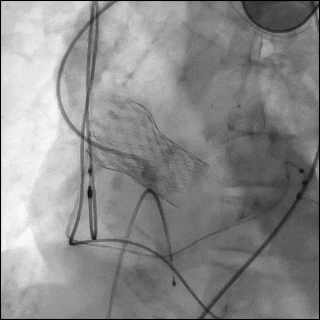

左前斜造影以获取最佳的瓣架对齐视角,可见 node 4 与 node 5 之间存在严重钙化,对应原Evolut R 瓣膜的瓣环上瓣叶区域。(图4,视频3)

图4 左前斜位瓣架对齐视图

在node4、node5之间可见严重钙化(白色箭头),对应原 Evolut R 瓣膜的瓣上小叶。